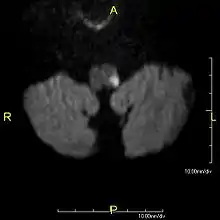

Since lateral medullary syndrome is often caused by a stroke, diagnosis is time dependent. Diagnosis is usually done by assessing vestibular-related symptoms in order to determine where in the medulla that the infarction has occurred. Head Impulsive Nystagmus Test of Skew (HINTS) examination of oculomotor function is often performed, along with computed tomography (CT) or magnetic resonance imaging (MRI) to assist in stroke detection. Standard stroke assessment must be done to rule out a concussion or other head trauma.[2]

- MRI of Lateral Medullary Infarction (Wallenberg) MedPix Images